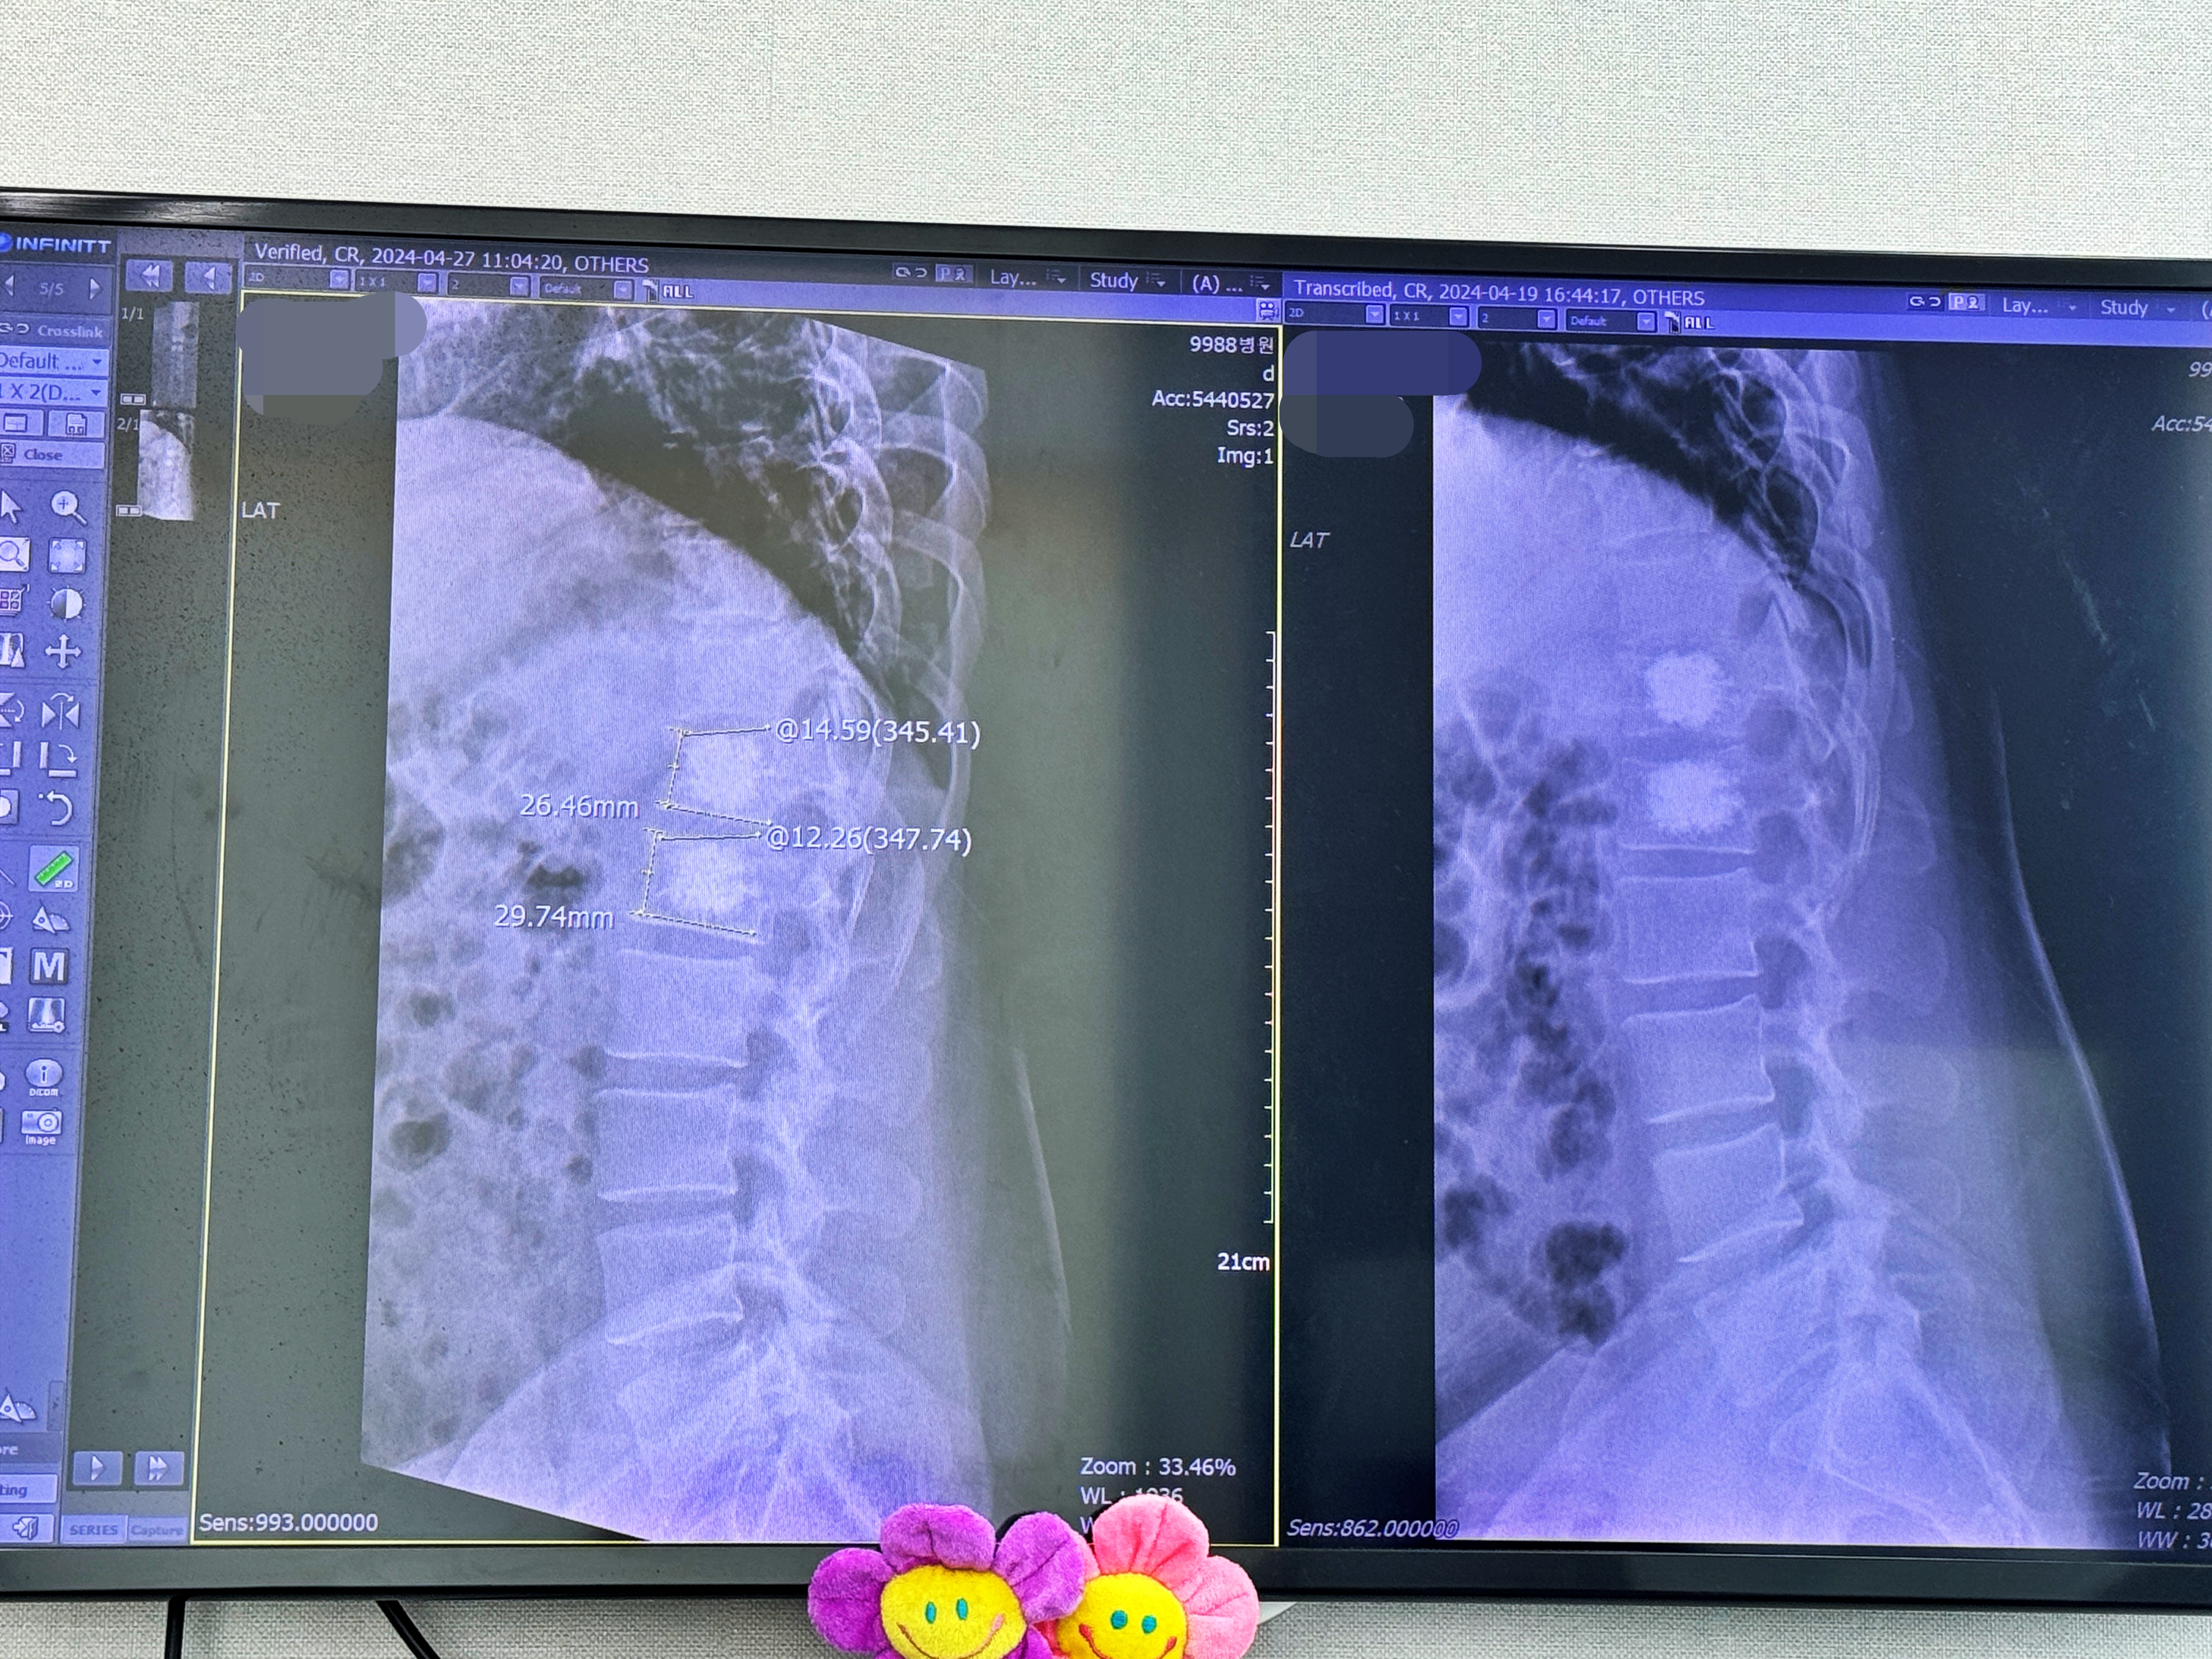

바로 지난주 촬영했던 X-RAY 사진과 비교합니다.

뼈가 잘 굳고 있고 큰 움직임은 없어 보인다고 하네요. 일상생활에 거의 무리가 느껴지지 않는다고 얘기하니 마약성 진통제도 빠지고 주사도 빠졌습니다. 보호대 착용 역시 2~3주 정도만 해도 될 것 같다고 하네요. 좋은 소식입니다. 그리고 앞으로는 1주일 주기가 아닌 2주 뒤 5월 둘째 주 토요일에 오라고 하시네요. 고로 병원비 부담도 줄었습니다. 토요일에 내원했음에도 제증명 포함 1.2만 원 수준의 병원비가 청구되는군요.